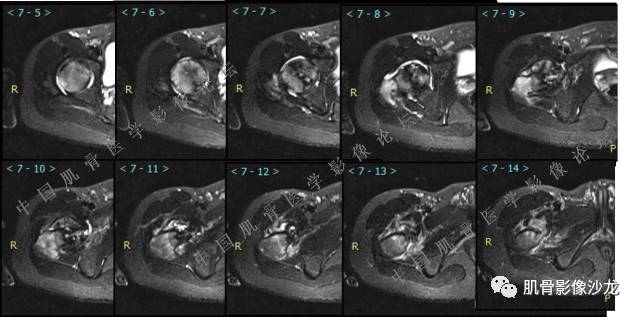

主诉:右大腿疼痛、活动受限20天

现病史:患者于20天前无明显诱因出现右下肢疼痛,活动受限,疼痛呈阵发性,活动后加重。自行口服止痛药芬必得,效果不佳,至当地医院治疗,检查发现右侧股骨近端病变。遂来诊

葛英霖 20:30 原发或继发动脉瘤样骨囊肿,继发于巨细胞瘤,软骨母,纤维组织细胞瘤,骨母等等

向以四 20:30 软骨母合并ABC,

医影在线 20:30 软骨母,/继发ABC

飞鹰行动 20:31 T2信号高,有软骨成分

Echo 20:32 T2确实有一块区域很亮 ,并有野液平

飞鹰行动 20:33 有侵袭性

飞鹰行动 20:35 骨皮质破坏,周围骨质异常信号

葛英霖 20:36 这不是良性病变

葛英霖 20:36 中间型可能性极大

葛英霖 20:37 明显侵蚀骨内膜啊,硬化边也不完整 (细箭头所示)

葛英霖 20:43 提不提也很明显继发了abc

葛英霖 20:44 是

葛英霖 20:46 明显的多囊状改变,液液平面